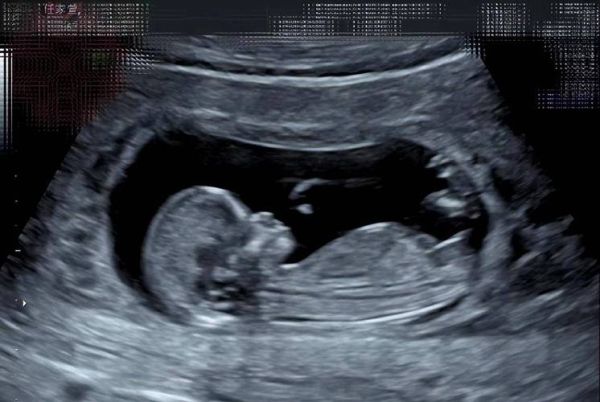

官方层面,我国禁止非医学需要的胎儿性别鉴定,正规医院不会在报告上标注性别。 但技术层面,B超确实能显示生殖器雏形,只是需要满足苛刻条件:

- 孕周:16周以后,外生殖器才初步分化;

- 体位:胎儿必须双腿张开,且无脐带遮挡;

- 设备:高分辨率彩超,由经验丰富的医师操作。

换句话说,“区别图”并非标准模板,而是极少数恰好拍到清晰生殖器的截屏,被私下流传后成了“神图”。